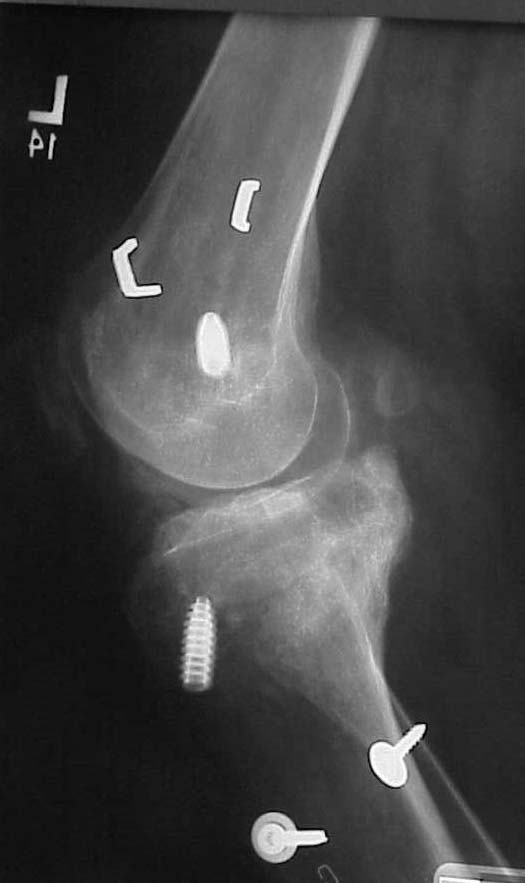

This is a 23 yo male that had a knee dislocation in Oct 2000 w/a popliteal artery injury repair and compartment syndrome and peroneal nerve injury that has not recovered.

He had STSG and delayed ACL/PCL and posterolateral corner reconstruction at 3 weeks. I only have his injury films, but he says his leg always has appeared to be in varus. He has a sedentary job, painless ROM 0-100 degrees, walks w/ slight limp. He made an appointment to establish a new physician as his insurance has changed. His clinical appearance and current xrays are impressive, but he does not seem too concerned. Any thoughts on interventions? He is getting his post reconstruction xrays for review.

Lat 18 mos

Varus